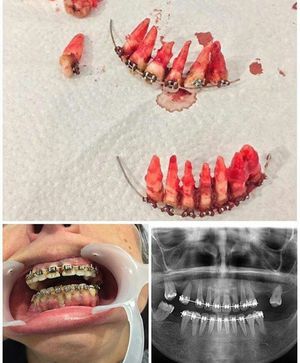

Why did they have to remove the whole tooth? (I'm a high school student)

It happen due to an periodontically treatet teeth befor putting bracket